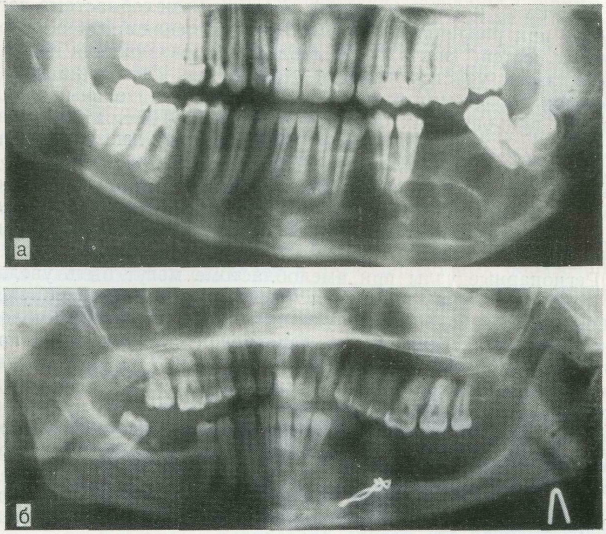

Одонтома нижней челюсти: фотографии и медицинская информация

Раздел: Фотобанк решений